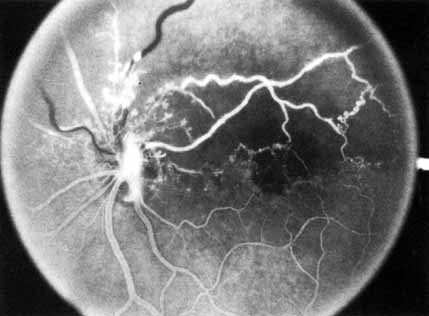

In the chronic phase, most hemorrhages gradually disappear over many months; however, scattered, flame-shaped hemorrhages and dot hemorrhages, particularly in the periphery, may be seen for years. Cotton-wool patches and microaneurysms likewise tend to disappear after several months, although in some cases the latter may persist. The venous tree becomes less tortuous and dilated. Prominent venous loops, which are collateral communications, may be observed on the surface of the disc (Fig. 6).85 These loops develop within 3 to 14 months after occlusion from the existing retinal vasculature and are collateral vessels between the obstructed disc capillaries and the unobstructed choroidal or pial capillaries.323 These retinochoroidal collateral veins, if they develop, may protect against anterior segment neovascularization,328 but may not be associated with a better visual prognosis.105 Collaterals between the central retinal vein within the globe and the patent central retinal vein behind the occlusion have not been observed.86 The extent and speed of retinal recovery probably depends to some degree on how quickly collateral vessels form, how rapidly recanalization occurs, and how adequately these compensatory mechanisms restore normal outflow. However, the exact nature and course of the collateral vessels are disputed. Anastomotic channels may develop within the retinal vasculature if pressure differentials develop between its major venous trunks. Changes in the retinal arterioles include both segmental and generalized narrowing as well as sclerosis, which is evidenced by both sheathing and widening of the light reflex. Sheathing of the veins is also common. The disc may appear nearly normal except for sheathing of the vessels in and around the papilla, and some blurring of the margins may persist. Sometimes optic atrophy is present.

Fig. 6 Fundus picture 4 years after central retinal vein occlusion. Moderate venous engorgement and small dot hemorrhages remain; microaneurysms, dot hemorrhages, and residual edema are present in the macula. Some sheathing of vessels is seen along with patchy edema residues. Note collateral channels on the retinal surface temporal to the disc and tortuous vessels on the surface of the disc representing collateral cilioretinal communications.

The fluorescein angiographic appearance varies greatly, depending on the extent of recovery. All the findings in the acute phase, consisting of venous and capillary engorgement, microaneurysms, staining of the veins, patchy extravascular fluorescence, and capillary nonperfusion, may persist indefinitely. In most instances, these findings eventually diminish so that few significant features are present on the angiogram; collateral vessels, if present, may be the only pathognomonic feature.